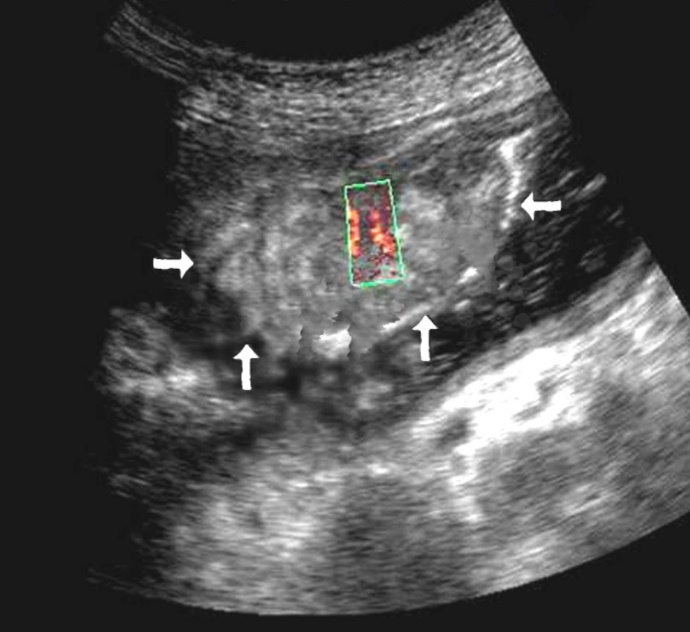

The polypoid type of gastric cancer was observed in 3 (4,9±2,8%) cases, the ulcerative type – in 18 (29,5±5,8%), the infiltrative ulcerative type – in 27 (44,3±6,4%) and the diffuse infiltrative type – in 13 (21,3%±5,2%) cases respectively (Table 2). On the echogram, the tumor was

Visualized as a polypoid formation on a wide base above the gastric mucosa of a non-uniform structure, an irregular surface (Figure 5, Figure 6, Figure 7).

Figure 5.The polypoid type of gastric carcinomas for T3 stage. On the posterior wall of the antrum, a polypoid formation with a fuzzy contour is visualized, the image of the mucous and serous membranes (arrows) is discontinuous.

Figure 6.The gastric carcinoma for T3 stage. The tumor is visualized as a polypoid formation on a wide base above the gastric mucosa of a non-uniform structure, an irregular surface (arrows).